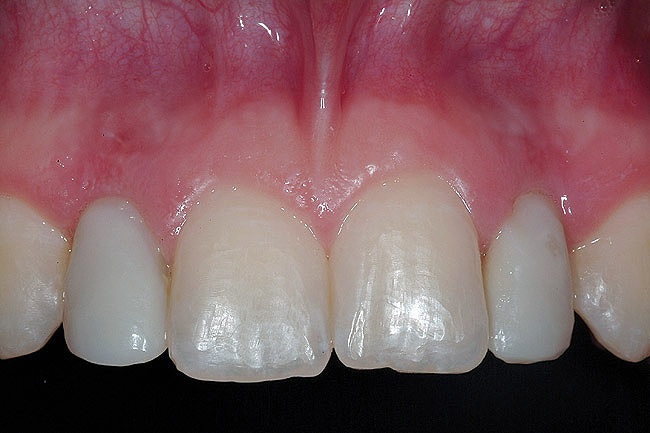

A 19-year-old non-smoking female presented for tooth replacement at the maxillary right and left lateral incisors, which were congenitally missing (Figure 1). The post-orthodontic result was adequate for the placement of 3-mm one-piece small-diameter implants. The preoperative radiographs can be seen in Figure 2 and Figure 3. The pretreatment clinical view in Figure 4 and Figure 5 shows the small intertooth space present in the lateral incisor areas. One of the most challenging tasks with congenitally missing lateral incisor cases is to create an acceptable soft tissue emergence profile from a crestal profile that is flat from the mesial of the canines to the distal of the centrals (Figure 4 and Figure 5). After pretreatment planning which consisted of a complete medical and dental history, radiographic analysis, and upper and lower study models mounted by a facebow transfer technique, the fabrication of a TempStent II surgical guide was completed. Figure 6 and Figure 7 show the occlusal view of the TempStent II guide on the study cast and in the oral cavity, respectively.

Figure 1  Pretreatment clinical view.

Figure 1

Figure 4  Pretreatment clinical view, right lateral incisor.

Figure 4

Figure 5  Pretreatment clinical view, left lateral incisor.

Figure 5